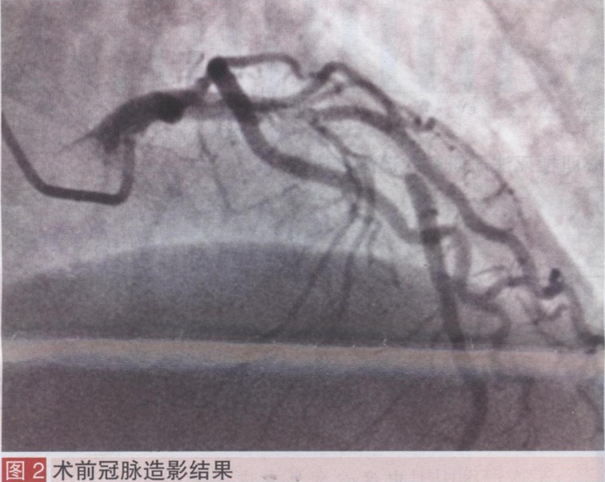

诊疗经过:于入院24 h内完成冠脉造影,术前予阿司匹林300 mg,氯吡格雷600mg,普通肝素100 IU/kg。冠脉造影示三支病变:左冠脉前降支(LAD)近段90-99弥漫性狭窄,前向TIMI血流3级(图2),左冠脉回旋支近段75%-85%带段性狭窄,前向TIMI血流3级,右冠脉近段60%-70%局限性狭窄,前向TIMI血流3级。